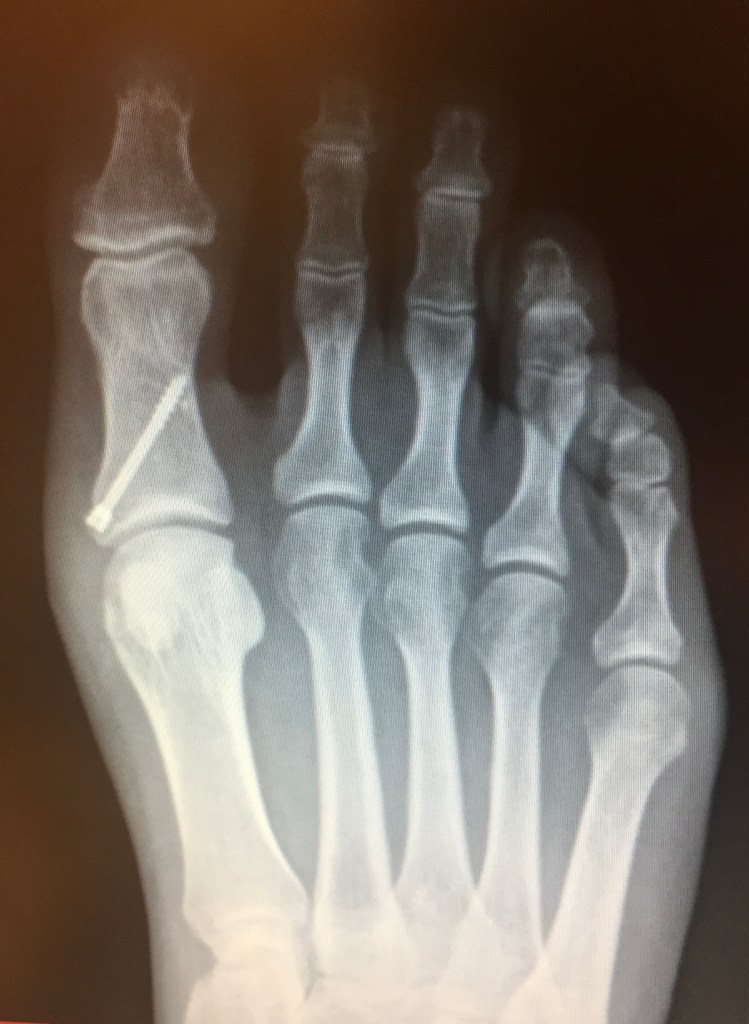

Take the cover image of this piece as an example. When the practitioner sees it through his medical gaze, he sees a successfully placed surgical screw into the proximal phalanx of the great toe on a right foot. Through this gaze, he doesn’t see the pain of the patient. He doesn’t see the ways it impacts her daily life, the pain in each step taken with that foot. He doesn’t see how it complicates the choices of where to park at a store, and limits her choice of footwear to one set of oversized tennis shoes. The meanings of medical images matters because if he saw what she sees, perhaps he would make time for practical questions of mobility or questions about healing from having such a surgery. He might shift his gaze from the objective success of the surgery to the subjective lived experience and impact it has on his patient. It might change the way he approaches the clinical conversation.